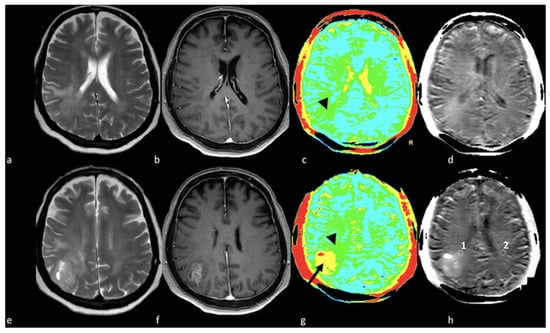

3.2. Diffusion Imaging Techniques

- Lee, E.J.; Ahn, K.J.; Lee, E.K.; Lee, Y.S.; Kim, D.B. Potential role of advanced MRI techniques for the peritumoural region in differentiating glioblastoma multiforme and solitary metastatic lesions. Clin. Radiol. 2013, 68, e689–e697. [Google Scholar] [CrossRef]

- Han, C.; Huang, S.; Guo, J.; Zhuang, X.; Han, H. Use of a high b-value for diffusion weighted imaging of peritumoral regions to differentiate high-grade gliomas and solitary metastases. J. Magn. Reson. Imaging 2015, 42, 80–86. [Google Scholar] [CrossRef] [PubMed]

- Lee, E.J.; terBrugge, K.; Mikulis, D.; Choi, D.S.; Bae, J.M.; Lee, S.K.; Moon, S.Y. Diagnostic value of peritumoral minimum apparent diffusion coefficient for differentiation of glioblastoma multiforme from solitary metastatic lesions. AJR Am. J. Roentgenol. 2011, 196, 71–76. [Google Scholar] [CrossRef] [PubMed]

- Sternberg, E.J.; Lipton, M.L.; Burns, J. Utility of diffusion tensor imaging in evaluation of the peritumoral region in patients with primary and metastatic brain tumors. AJNR Am. J. Neuroradiol. 2014, 35, 439–444. [Google Scholar] [CrossRef]

- Neska-Matuszewska, M.; Bladowska, J.; Sasiadek, M.; Zimny, A. Differentiation of glioblastoma multiforme, metastases and primary central nervous system lymphomas using multiparametric perfusion and diffusion MR imaging of a tumor core and a peritumoral zone-Searching for a practical approach. PLoS ONE 2018, 13, e0191341. [Google Scholar] [CrossRef]